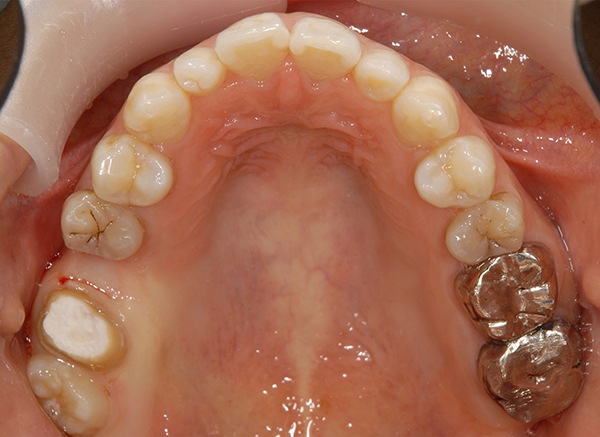

親知らずを大臼歯として生え変わらせたケース

上顎の左右第二大臼歯の予後が悪い為に抜歯を行い、親知らずが大臼歯の場所に生え変わるまで待ちました

抜歯後、親知らずが徐々に生えてきいき健全な歯に生え変わりました。

治療期間 3年

費用 抜歯2本5,000円